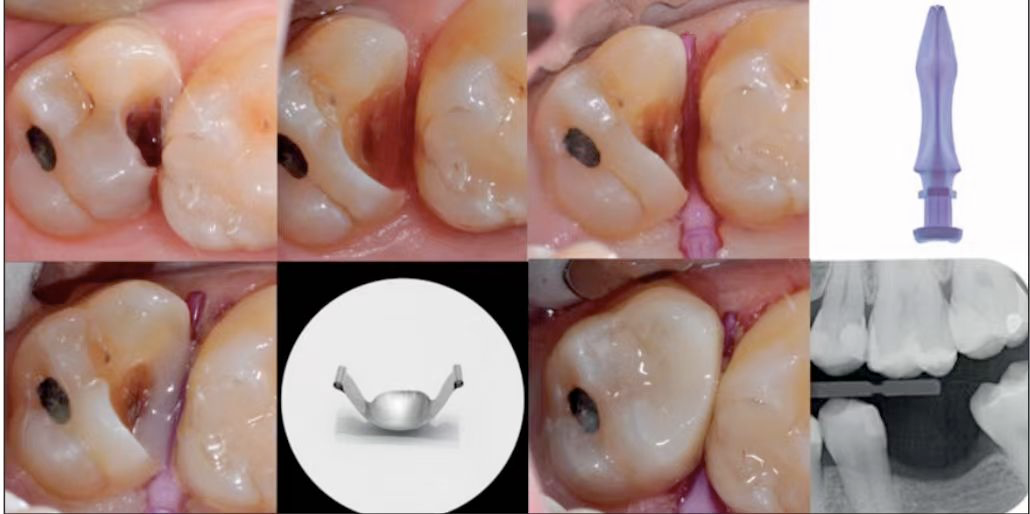

图8:通过解剖楔子的辅助形成的的DME。使用Bioclear生产的Sabre和Diamonds等解剖楔子,可以同时管理DMS和儿科牙科的DME。

由Bioclear成型系统DME,在儿牙根管治疗领域是非常有用的,并且非解剖的DME不需要任何辅助隔离的情况下填充材料,通过徒手操作进行平整修复,使用特氟龙来增强非解剖DME的治疗效果。非解剖DME操作相对简单,对技能和专业知识要求较低,同时,在某些特殊情况种选择不使用成型装置也是可行的,这样可以减少出血的情况和保持封闭。

橡皮障隔离患牙,去净腐质,然后进行详细的生物力学分析,远中舌尖无牙本质支撑,需要牙尖覆盖,降低1.5mm左右,远中颊尖厚度足够。近中邻面边缘嵴完整,远中邻面边缘需要进行CMR。

圈型成型片完美隔离,喷砂牙本质表面,将牙本质表面进行37%磷酸酸蚀15秒,轻轻风干5秒后涂布粘接系统,进行IDS。

进行IDS,远中邻面进行CMR